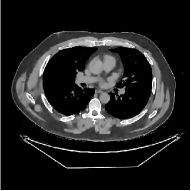

This section compares the reconstruction quality and runtime among the proposed MBIR method, PWLS-ST-, and other three MBIR methods, PWLS-EP, PWLS-DL, and PWLS-ST-. Table I shows that, for both 2D and 3D sparse-view CT reconstructions of the XCAT phantom, the proposed PWLS-ST- model outperforms PWLS-EP and PWLS-ST- in terms of RMSE. In addition, PWLS-ST- using a square transform (of size ) achieves lower RMSE than PWLS-DL using an overcomplete dictionary (of size ) for 2D sparse-view reconstructions. Fig. 3(a) and Fig. 4 show the reconstructed images for 2D and 3D phantom experiments, with different reconstruction models and different number of views. (See the corresponding error maps in the supplement.) The proposed PWLS-ST- consistently gives more accurate image reconstructions compared to other MBIR methods. Specifically, PWLS-ST- has smaller errors in the heart region (see zoom-ins in Fig. 3(a)) of 2D reconstructions than PWLS-DL and PWLS-ST-. In addition, compared to PWLS-ST-, PWLS-DL and PWLS-ST- have some ringing artifacts around the edges with high transition, e.g., edges between air and soft tissues. (See a comparison of profiles of PWLS-ST- and PWLS-ST- in the supplement.) In particular, PWLS-ST- and PWLS-DL give more visible ringing artifacts for 2D reconstruction from fewer views, and PWLS-ST- has these ringing artifacts for 3D reconstructions regardless of the number of views (see zoom-ins in Fig. 4). Table II reports runtimes of different MBIR methods in reconstructing the -views XCAT phantom scan. (FBPConvNet is a non-MBIR method and its runtime for processing a image is approximately one second with a TITAN Xp GPU.) While providing better reconstruction quality, the proposed Algorithm 1 of PWLS-ST- has shorter runtime compared to the algorithms of PWLS-DL and PWLS-ST- in Section III-A. Similar to the PWLS-EP algorithm, the reconstruction time of the PWLS-DL, PWLS-ST-, and PWLS-ST- algorithms can be further reduced by using ordered subsets [51].

| (b) 3D axial cone-beam CT experiments |